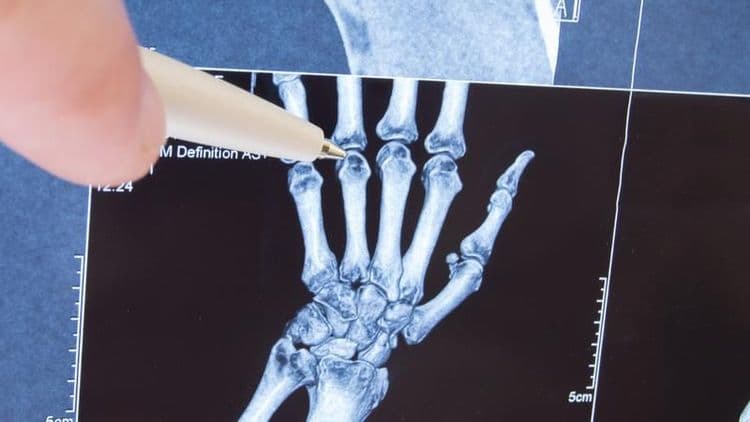

मंडळी, डॉनाल्ड उंगर यांनी ५० वर्षात डाव्या हातांची बोटे रोज २ वेळा मोडली. उजव्या हाताने जोर द्यायचा आणि डाव्या हाताची बोटे मोडायची हा त्यांचा रोजचा क्रम होता. त्यांनी स्वतः सांगितल्याप्रमाणे त्यांनी डाव्या हाताची बोटे तब्बल ३५,५०० वेळा मोडली. उजव्या हाताची बोटे ते फारच क्वचित मोडत. त्यांच्या स्वतःच्या शब्दात सांगायचं झालं तर ‘क्वचित किंवा उत्स्फूर्तपणे’.

तर, हे करण्यामागचं कारण होतं संधिवात खरंच होतो का हे पाहणं. बोटं मोडून झाली की ते स्वतःच्या हातांचं परीक्षण करायचे. शेवटी त्यांच्या लक्षात आलं की बोटं मोडल्याने संधिवात होतो ही फक्त एक अफवा आहे. ते यावर आणखी संशोधन करण्याच्या तयारीत आहेत. हे सगळं करत असताना त्यांना प्रश्न पडला की लहान मुलांना आणखी कोणकोणत्या खोट्या गोष्टी शिकवल्या जातात? कदाचित यावर पण ते संशोधन करतील.

नाही!! उंगर यांचं संशोधन बाहेर येण्यापूर्वी माणसांच्या बोटांवरचं संशोधन हे फारच जुनाट झालं होतं. उंगर यांच्यामुळे विज्ञानाच्या हाती नवीन संशोधन लागलं. तसेच नवीन संशोधनास चालना मिळाली.